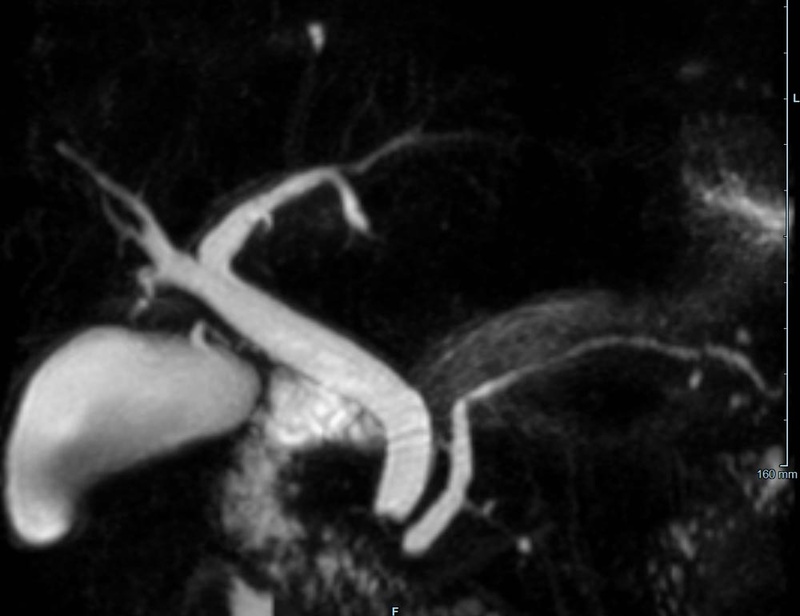

• Gallenwegssystem

• Nichtinvasive Darstellung der Gallenwege (MRCP)

• Abklärung der Ursache einer Gallenabflussbehinderung (Tumor, Gallensteine, Entzündung)

• Pankreas

• Diagnostik des Pankreaskarzinoms und Pankreasentzündung

• weitere Einordnung von Pankreaszysten (z.B. Pseudozysten, IPMN)

• Therapieverlaufskontrolle